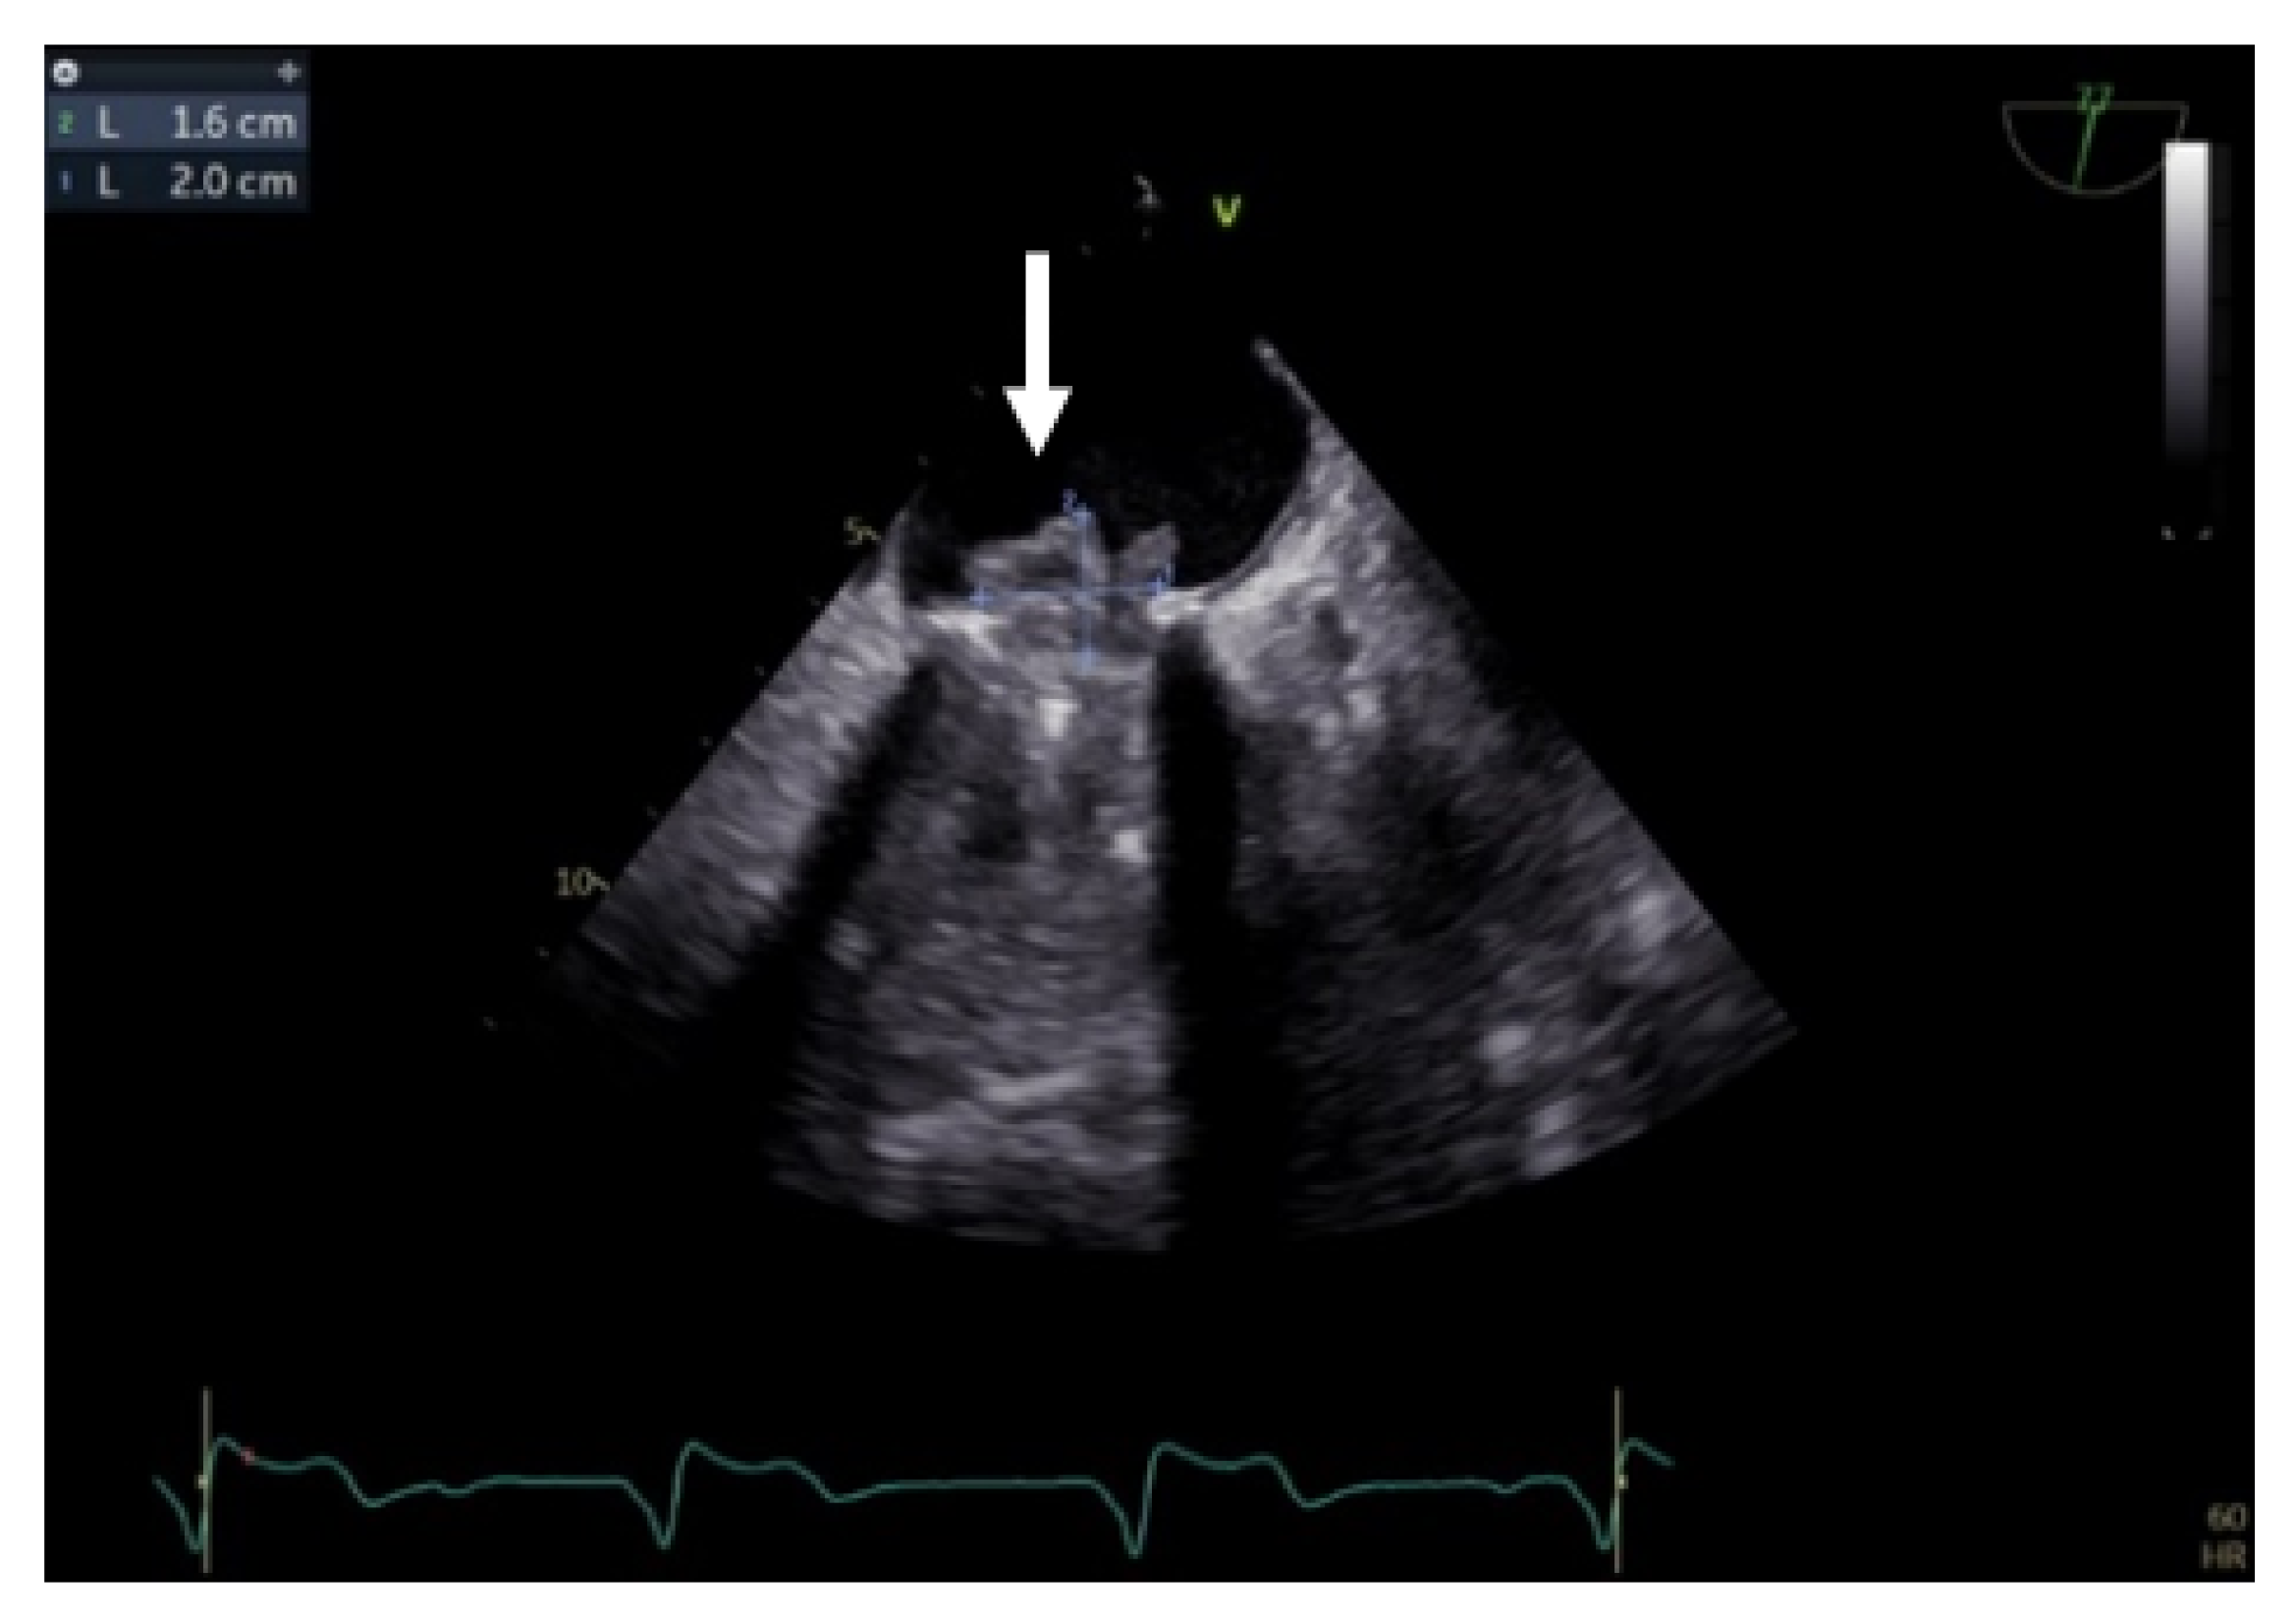

Transgastric and deep transgastric TEE views are helpful for measuring the transprosthetic gradients and LVOT diameter in order to calculate the effective area of the aortic prosthesis. Useful information is also obtained from the mid-esophageal view at 80°, where the prosthesis is visualised in a short-axis view (Figure 10). The mobility of the discs, the symmetry of their closing–opening, and the evaluation of intra- or paraprosthetic leaks are described [13]. Stress echocardiography could be beneficial in cases of uncertain diagnosis, where the assessment of the increased transprosthetic gradient is correlated with symptom reproduction. A significant increase in the gradient through the prosthesis suggests obstruction of the aortic prosthesis [13].

Figure 10.

TEE. Nonobstructive thrombus on the aortic prosthesis ring (arrow).